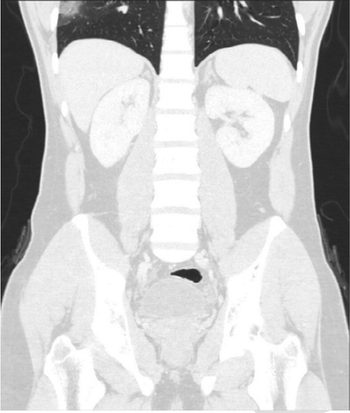

Results show COVID-19-positive patients with BMI greater than 30 are at significantly higher PE risk.

Affected patients were sicker and more likely to be admitted to the ICU.